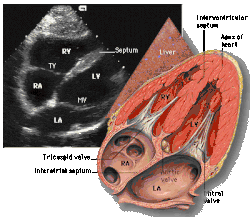

![]() Subcostal four chamber |

| Each figure contains a TTE with a black background, and a corresponding colored illustration. | Patrick J. Lynch and C. Carl Jaffe, Yale University, 2006. | ||||||||||

| Click on a figure to enlarge it and see some parts of the heart identified. RV, right ventricle; LV, left ventricle; RA, right atrium; LA, left atrium; TV, tricuspid valve; MV, mitral valve; AV, aortic valve; RVOT, right ventricular outflow tract; LVOT, left ventricular outflow tract | |||||||||||